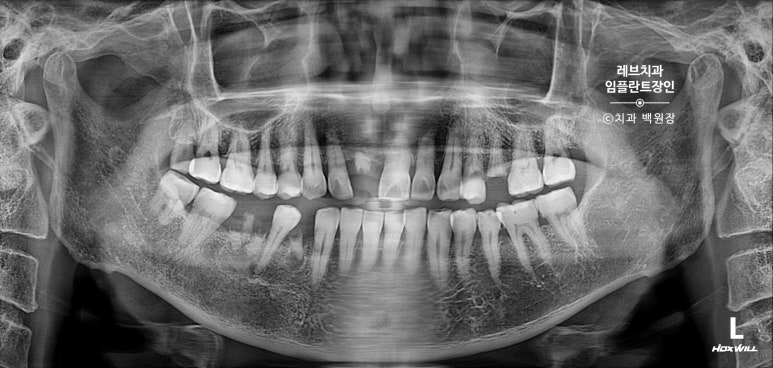

치과용 파노라마 사진을 보시면, 아주 짧은 뿌리만이 남아있는 것을 보실 수 있어요..

고개를 돌려서 보면, 뿌리만 있는 치아들이 몇개 보이고...

치아 목부위 (치경부)에 충치가 있는 치아들도 여러개 보여요.